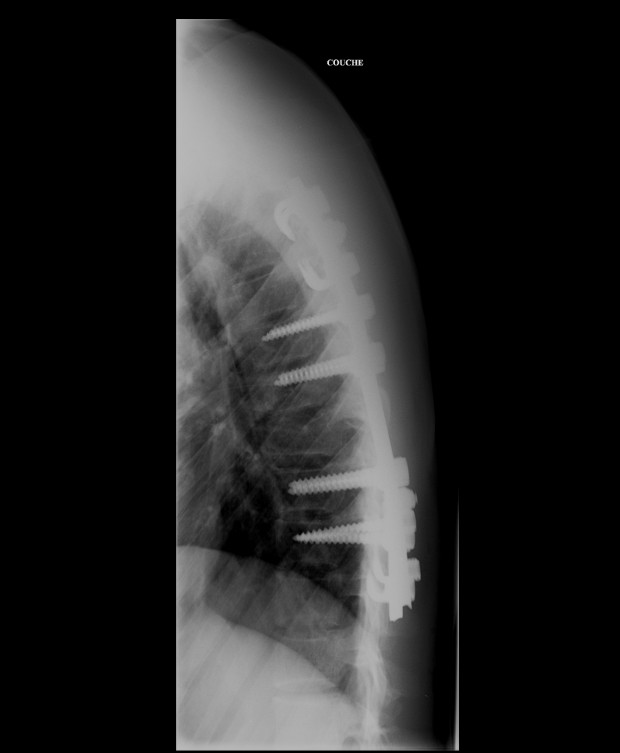

By Wednesday 10th there was a clear plan by the surgeons – Dan relayed to me the intention to fuse some of the vertebrae together – which sent alarm bells off in my head as I was already thinking about Tay’s return to sport. A spinal fusion is something rugby players can and do have, and carry on playing. However given how young Tay is, I didn’t think this was the way to go – however it was then changed to a fixation. This meant they were going to put titanium rods either side of the fracture site. Again, the degree of ‘fixation’ can vary and the intention was to rod the damaged vertebra, the ones immediately above and below. I was really keen to have Tay flown back to UK and taken straight to the back specialist I use, however the insurance would not fly Tay out of France without the operation. This is entirely understandable as the bones can and do displace in flight. Some companies are prepared to have the patient as immobilised as possible and fly them, whilst others insist the surgery is carried out. I reminded everyone involved that the hospital that Tay was being treated in Grenoble likely dealt with 100′s of surgeries similar with recreational skiers throwing themselves down the mountain in the winter and were probably more than capable.

Having had such a major operation, the short term treatment once back in the UK was to rest to allow some healing. Tay had some rudimentary guidelines from the doctors in France, but essentially it was rest he needed. I also advised his parents to take him to the GP as soon as possible, something I wouldn’t normally do but Tay would need some decent post op care, which meant reporting to the GP to get some NHS resources to swing into action. Unfortunately the GP experience was a massive ‘computer says no’. As helpful as the GP tried to be, due to Tay having the operation in France this meant referring him onto a specialist would take a few weeks before he was able to see anyone about his back. Figuring that the GP route would get bogged down in red tape, I’d already placed some calls and got Tay to the one of the WRU ‘go to’ guys for spinal injuries – Dr Stuart James – as we really needed an urgent expert opinion on exactly what operation Tay had carried out on him and what the next steps were. Big thanks to elite physio Tim Atter for helping out with setting all that up. When Tay’s dad sent me the images and scans – it was fairly shocking, even for me.

I actually had never seen that level of fixation in the spine, and even to me it looked a bit ‘over’ fixated and certainly not the relatively minor fixation described by the doctors before the op. I was also thinking about how young Tay was and any considerations needed with growth. Meeting with the specialist surgeon in Wales, he too felt he wouldn’t have gone with quite so much fixation – but every surgeon is different. Regardless of the operation it’s what happens post op and how that’s managed which is going to have the most positive effect. The thing to do now was come up with a plan, so me and team fitness coach Alan Milway sat down and began working it all out…